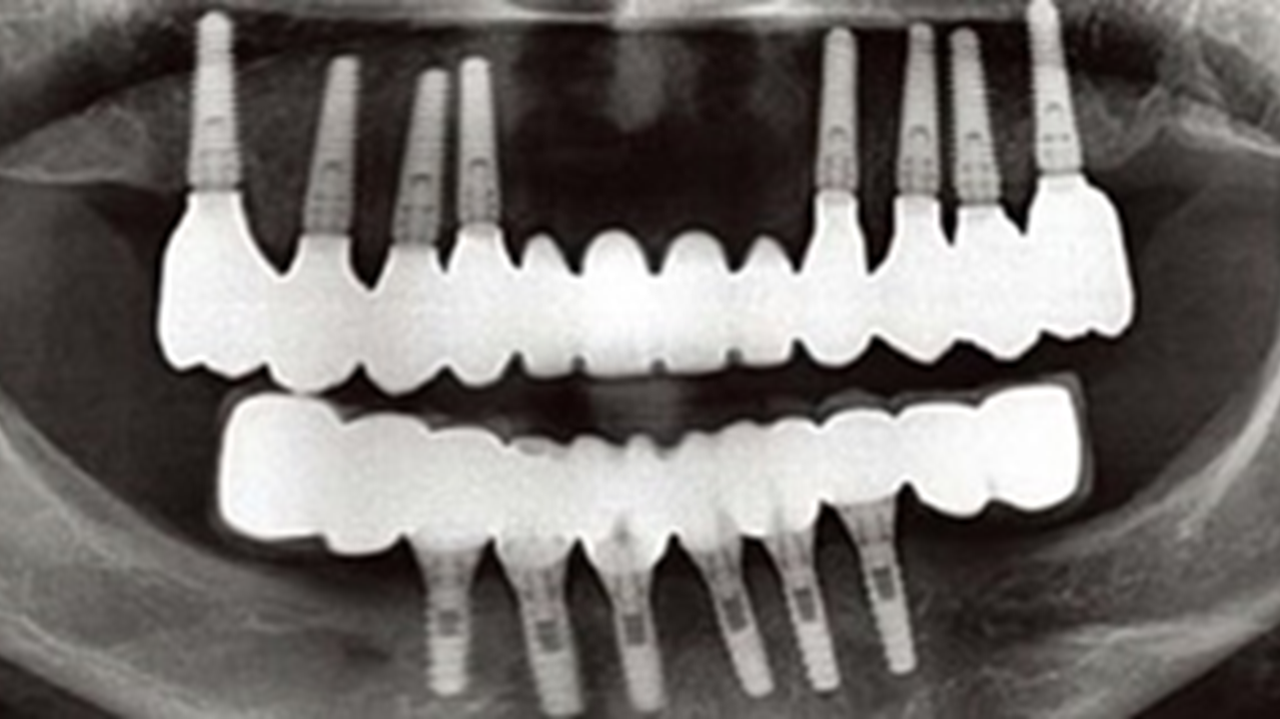

Clinical case: Full-mouth implants for mandibular & maxilla - restored using mixed prostheses

- Courtesy of Dr. Hyun Jun Kim, Korea -

Keywords

AnyRidge, full-mouth implants, mandibular, maxilla, edentulous, full mouth rehabilitation, Octa abutment, long-term clinical case, biological stability, Dr. Hyung Jun Kim

Products:

AnyRidge implant system